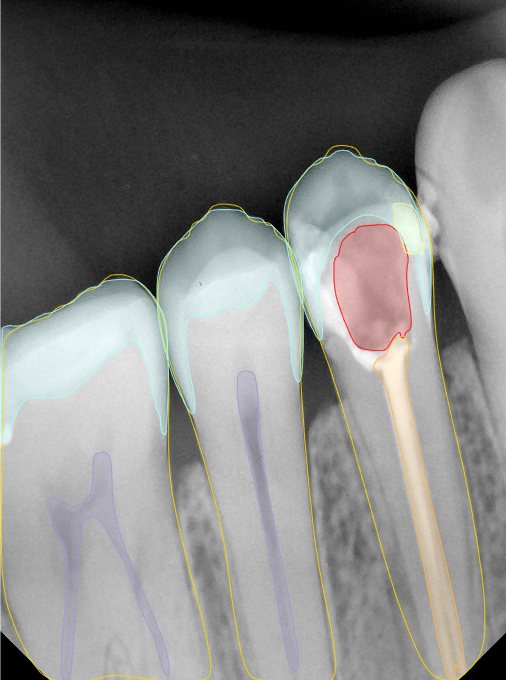

CR/DR 牙齿分割阶段记录

当前进展

- 完成了 CR/DR 牙齿相关分割训练

- 当前结果已经达到阶段预期,但仍有细节问题需要继续处理

相关测试

遇到的问题

- 训练过程中出现过 mask 下移问题

- 部分结果会出现 box 填充异常

- mask 边缘仍然有比较明显的锯齿感

参考

第二版算法问题测试

Updated: 2026-04-13(更新日期)

| 第一版 | 第二版 | 是否解决 | |

|---|---|---|---|

![]() | ![]() ![]() 边角识别有问题 龋齿识别不全 牙髓识别不全 | ![]() | 解决 |

![]() | ![]() 边角识别有问题 识别信息有误 自查(牙冠识别不全) | ![]() | 解决 |

![]() | ![]() ![]() 边角识别有误 大范围填充识别遗漏 | ![]() | 解决 |

![]() | ![]() 识别信息不全 | ![]() | 解决 |

![]() | ![]() ![]() 边角问题 牙胶识别不全 牙冠识别不全 | ![]() | 解决 |

![]() 换图片 | ![]() | ![]() 牙冠部分稍微白了一些就识别成小范围修补,部分判断异常 | 部分解决,修复类略敏感,牙冠部分稍微白了一些就识别成小范围修补,部分判断异常。 |

![]() | ![]() ![]() 牙冠识别不全 牙髓不全 根尖炎龋齿识别有误 | ![]() | 解决 |

![]() | ![]() | ![]() | 解决 |

![]() 换图片 | ![]() | ![]() | 解决 |

![]() | ![]() 牙冠识别有误 | ![]() | 解决 |

![]() 换图片 | ![]() ![]() 边角识别有误 | ![]() 修复类敏感 | 部分解决,图像过白,导致修复类判断异常。 |

![]() 换图片 | ![]() 牙冠识别不全 | ![]() 修复类敏感 | 部分解决,图像过白,导致修复类判断异常 |

结论:修复类出现了不鲁棒的情况,后续需要加入轮廓的扩充数据进行增强。